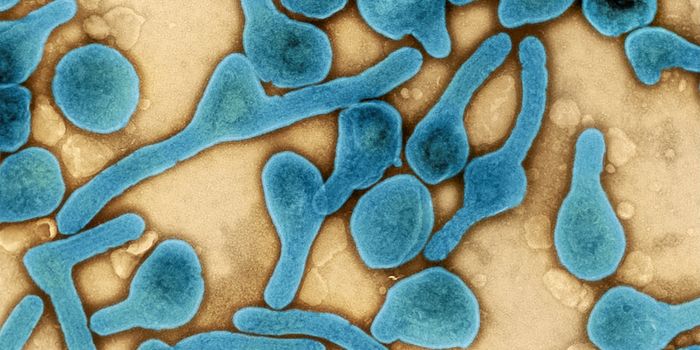

JUL 18, 2022MicrobiologyFor the first time, Marburg virus has been detected in Ghana after two people died from the disease. Marburg virus is si ...